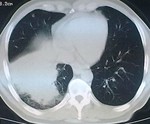

Оказываетя, что за год до этого пациенту была удалена опухоль на бедре, гистологически синовиальная саркома. Было произведено КТ ОГК. Подтвердили пневмонию, мета в позвоночник.

Не зная, что была такая операция (больной вначале это притаил, видимо не хотел к этому возвращаться) я предположил БАР, но компъютерщики развеяли мои подозрения. Поэтому я бы хотел знатоков КТ-дела проанализировать сканы, все ли там в порядке с корнем и т.д.

Пневмонии тут нет никаким боком. Не было КТ - высказался бы за БАР. На КТ, в легких -типичный раковый лимфангаит (кстати, слева тоже, еще чуть-чуть и полыхнет). Так что, 100% метастазирование. И это кроме очевидного метастаза в позвонок. А корень надо оценивать в "медиастинальном" окне.